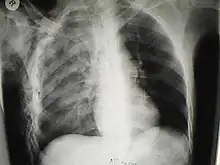

Significant cases of subcutaneous emphysema are easy to diagnose because of the characteristic signs of the condition.[1] In some cases, the signs are subtle, making diagnosis more difficult.[13] Medical imaging is used to diagnose the condition or confirm a diagnosis made using clinical signs. On a chest radiograph, subcutaneous emphysema may be seen as radiolucent striations in the pattern expected from the pectoralis major muscle group. Air in the subcutaneous tissues may interfere with radiography of the chest, potentially obscuring serious conditions such as pneumothorax.[18] It can also reduce the effectiveness of chest ultrasound.[27] On the other hand, since subcutaneous emphysema may become apparent in chest X-rays before a pneumothorax does, its presence may be used to infer that of the latter injury.[13] Subcutaneous emphysema can also be seen in CT scans, with the air pockets appearing as dark areas. CT scanning is so sensitive that it commonly makes it possible to find the exact spot from which air is entering the soft tissues.[13] In 1944, M.T. Macklin and C.C. Macklin published further insights into the pathophysiology of spontaneous Macklin's Syndrome occurring as a result of a severe asthmatic attack.